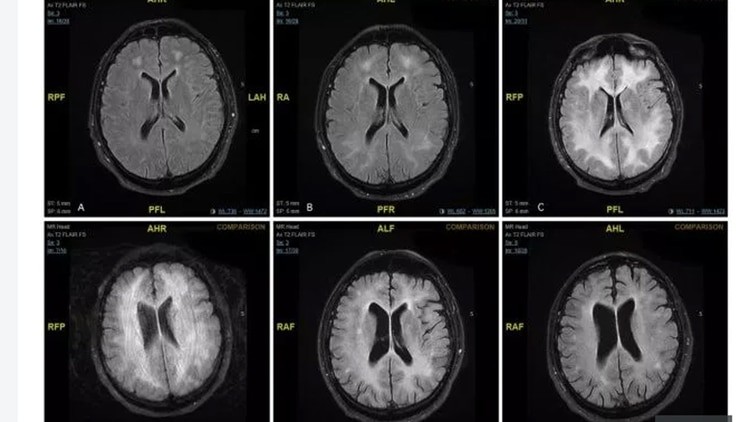

Las imágenes del cerebro obtenidas a través de estudios de resonancia magnética de un consumidor habitual de cocaína revelan el daño que la droga puede causar con el tiempo.

El paciente no identificado fue diagnosticado con una condición rara llamada leucoencefalopatía tóxica inducida por cocaína después de abusar regularmente durante años.

Los estudios fueron efectuados en el hospital de Msida, de Malta. Según los profesionales que atendieron al paciente, se trata de un hombre de 45 años que estaba confundido y se comportaba de manera extraña, antes de que los médicos se dieran cuenta de que padecía leucoencefalopatía tóxica inducida por cocaína.

Abdilla envió a su paciente para una resonancia magnética en su cerebro, que reveló daños en la sustancia blanca en el cerebro.

Un año después de ser ingresado en el hospital, el hombre regresó para un seguimiento. No había usado drogas durante un año, y aunque su escáner cerebral aún mostraba "cambios persistentes en la materia blanca", las pruebas neurológicas eran normales.